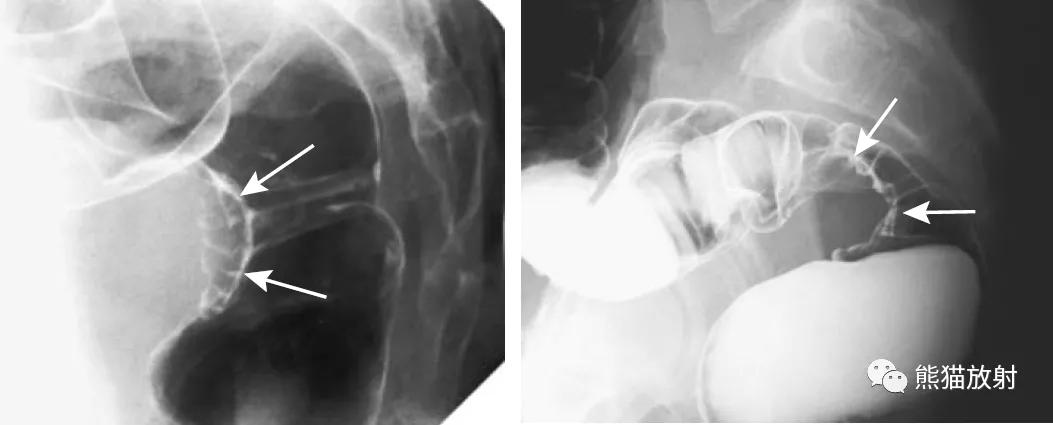

盲肠扭转。X线摄片显示中腹部肠管明显扩张(箭头)。钡餐检查示升结肠扭曲部位可见特征性的鸟嘴征(箭头)。

乙状结肠扭转。消化道造影侧视图可见乙状结肠局部走行扭曲(箭头)。